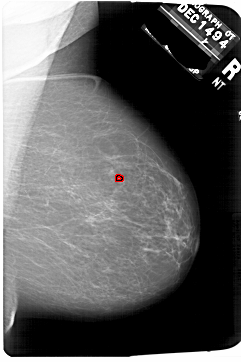

A_1751_1.RIGHT_MLO

RIGHT_MLO LINES 6871 PIXELS_PER_LINE 4576 BITS_PER_PIXEL 12 RESOLUTION 43.5 OVERLAY

FILE: A_1751_1.RIGHT_MLO.OVERLAY

TOTAL_ABNORMALITIES 1

ABNORMALITY 1

LESION_TYPE CALCIFICATION TYPE PLEOMORPHIC DISTRIBUTION CLUSTERED

ASSESSMENT 4

SUBTLETY 2

PATHOLOGY BENIGN

TOTAL_OUTLINES 1

BOUNDARY